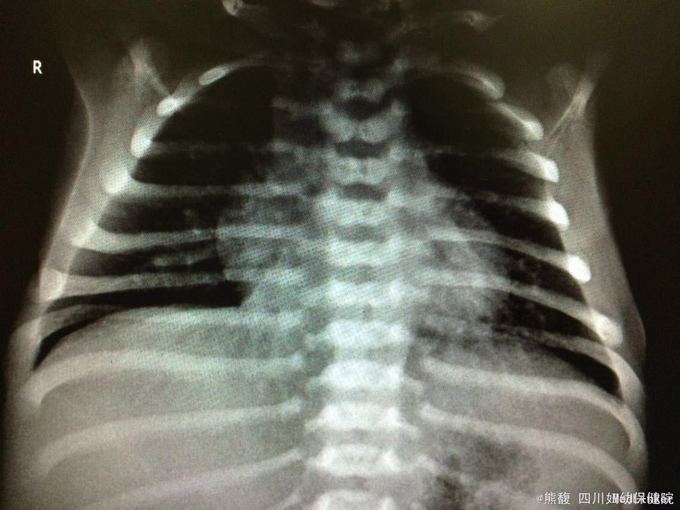

该患儿没有多少线索,看到他的胸片,好像是蝴蝶样的椎骨,如果是的话,也算是一点线索吧,继续追踪。